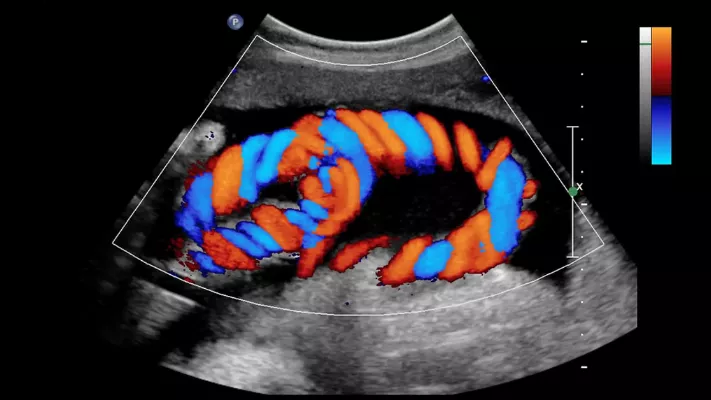

Color Doppler

Our hospital provides advanced Color Doppler Study services to assess blood flow through arteries and veins using high-resolution ultrasound technology. This non-invasive and painless test helps in the accurate diagnosis of various vascular and cardiac conditions.